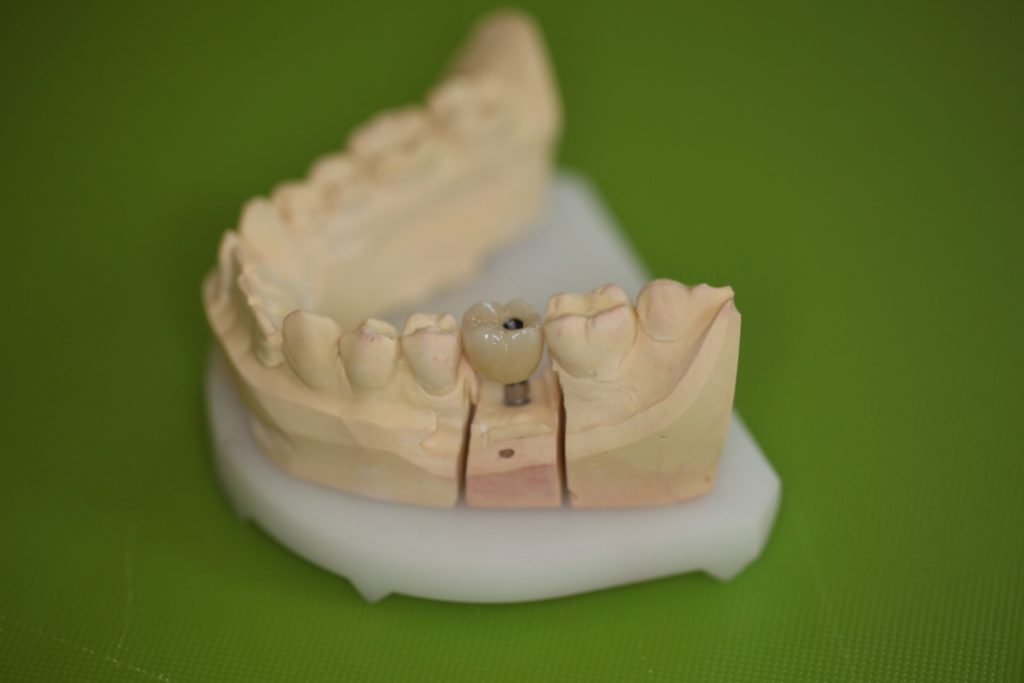

Side view of the screw-retained implant crown intended for the lower left first molar on a gypsum cast.

Upper view of the screw-retained implant crown intended for the lower right left molar on a gypsum cast.

Lingual side view of the screw-retained implant crown intended for the lower left first molar on a gypsum cast.